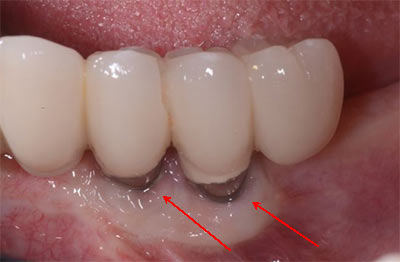

According to a study, infection and inflammation are among dental implants’ most common side effects. These are known as “peri-implants,” and they result from bacteria building up around the implant. Bacteria buildup may happen due to poor oral hygiene, improper implant placement and other pre-existing issues such as diabetes and gum disease. Also smoking and putting excessive force on the implants can also contribute to this problem. Treatment for infection may include antibiotics or deep cleaning. Surgical intervention may be required to remove the infected area and regenerate the bone if the condition is severe. Take a look at dental implant infection pictures below:

What are the dental implant infection signs to look for? The signs may include:

- The infected implant may result in redness and swelling around the implant sites

- Pus or discharge around the implant sites is a clear indication of an infection

- The loose or unstable feeling of the implant may be due to an underlying infection affecting the bone.

- Infection can also cause a low-grade fever.

According to a research, peri-implantitis can take around 5 years to progress and result in symptoms. If you notice any of these dental implant infection signs after getting a dental implant, you should promptly contact your medical professional without waiting.